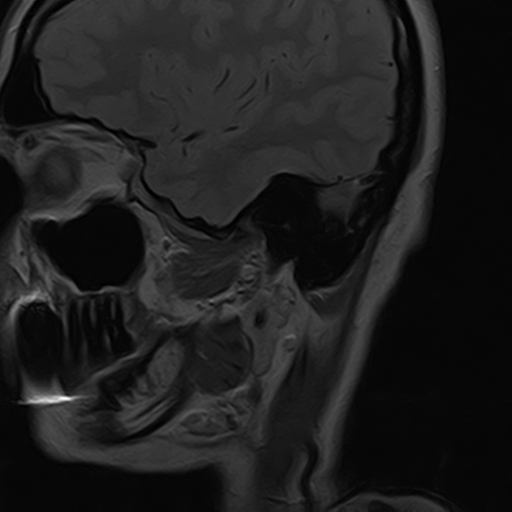

Чаще всего дисфункция височно-нижнечелюстного сустава обусловлена внутренним повреждением, смещением мениска и суставной головки нижней челюсти. Для определения степени смещения внутрисуставных структур выполняется функциональная проба с проведением МРТ в двух положениях:

• с закрытым ртом;

• с открытым ртом.

Магнитно-резонансная томография является наиболее точным и эффективным методом диагностики поражения височно-нижнечелюстных суставов, так как позволяет получить детальную информацию о состоянии не только костей, но и связочного аппарата, хрящей, менисков, жевательных мышц, окружающих мягких тканей.

При проведении магнитно-резонансной томографии на изображениях визуализируются: височная кость, головка мыщелкового отростка нижней челюсти, суставная щель. Помимо костных структур МРТ позволяет оценить состояние мягких тканей – внутрисуставного диска и связочного аппарата височно-нижнечелюстного сустава, жевательных мышц.

Протокол МРТ ВНЧС предусматривает проведение исследования в двух положениях: с открытым ртом и закрытым ртом. Данная функциональная проба дает возможность оценить биомеханику работы височно-нижнечелюстного сустава.